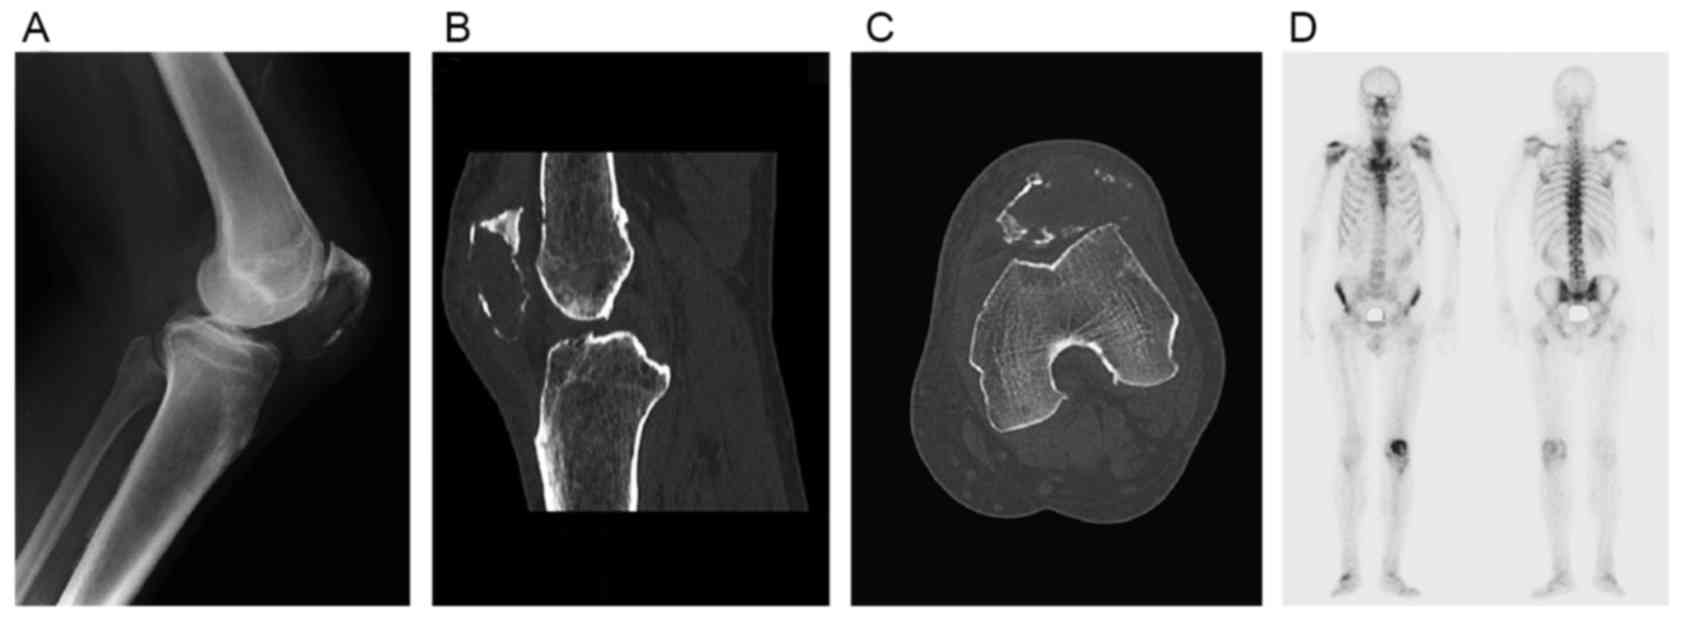

Patellar metastasis from primary tumor (Review)

Although bone tumors are frequently located in the knee area, primary tumors of the patella are rare and patellar metastases are even rarer. Knee pain is the most common complaint of patients with patellar metastases. Owing to the low incidence of patellar metastases, misdiagnosis is not unusual. The present review analyzes ~44 cases of patellar metastases originating from distinct primary sites. Reports of malignant tumors of the lung and kidney metastasizing to the patella were more common than those of other patellar metastases. Relative incidence, symptomatology, imaging features, histopathology and treatment options for these patellar metastatic lesions are described respectively along with a review of the literature. Despite numerous experiments demonstrating the reasons for implantation of tumor in patella, the answer to this question has not yet been revealed. In the light of the increasing attention on the diagnosis and the treatment of these lesions, the availability of the integrated information regarding metastases in the patella becomes more relevant.

Figure 2